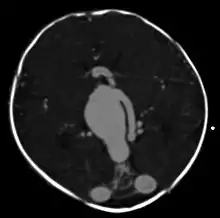

| Large arteriovenous malformation of the parietal lobe | |

vein of Galen malformation

A cerebral AVM diagnosis is established by neuroimaging studies after a complete neurological and physical examination.[5][12] Three main techniques are used to visualize the brain and search for an AVM: computed tomography (CT), magnetic resonance imaging (MRI), and cerebral angiography.[12] A CT scan of the head is usually performed first when the subject is symptomatic. It can suggest the approximate site of the bleed.[3] MRI is more sensitive than CT in the diagnosis, and provides better information about the exact location of the malformation.[12] More detailed pictures of the tangle of blood vessels that compose an AVM can be obtained by using radioactive agents injected into the blood stream. If a CT is used in conjunction with an angiogram, this is called a computerized tomography angiogram; while, if MRI is used it is called magnetic resonance angiogram.[3][12] The best images of a cerebral AVM are obtained through cerebral angiography. This procedure involves using a catheter, threaded through an artery up to the head, to deliver a contrast agent into the AVM. As the contrast agent flows through the AVM structure, a sequence of X-ray images are obtained.[12]